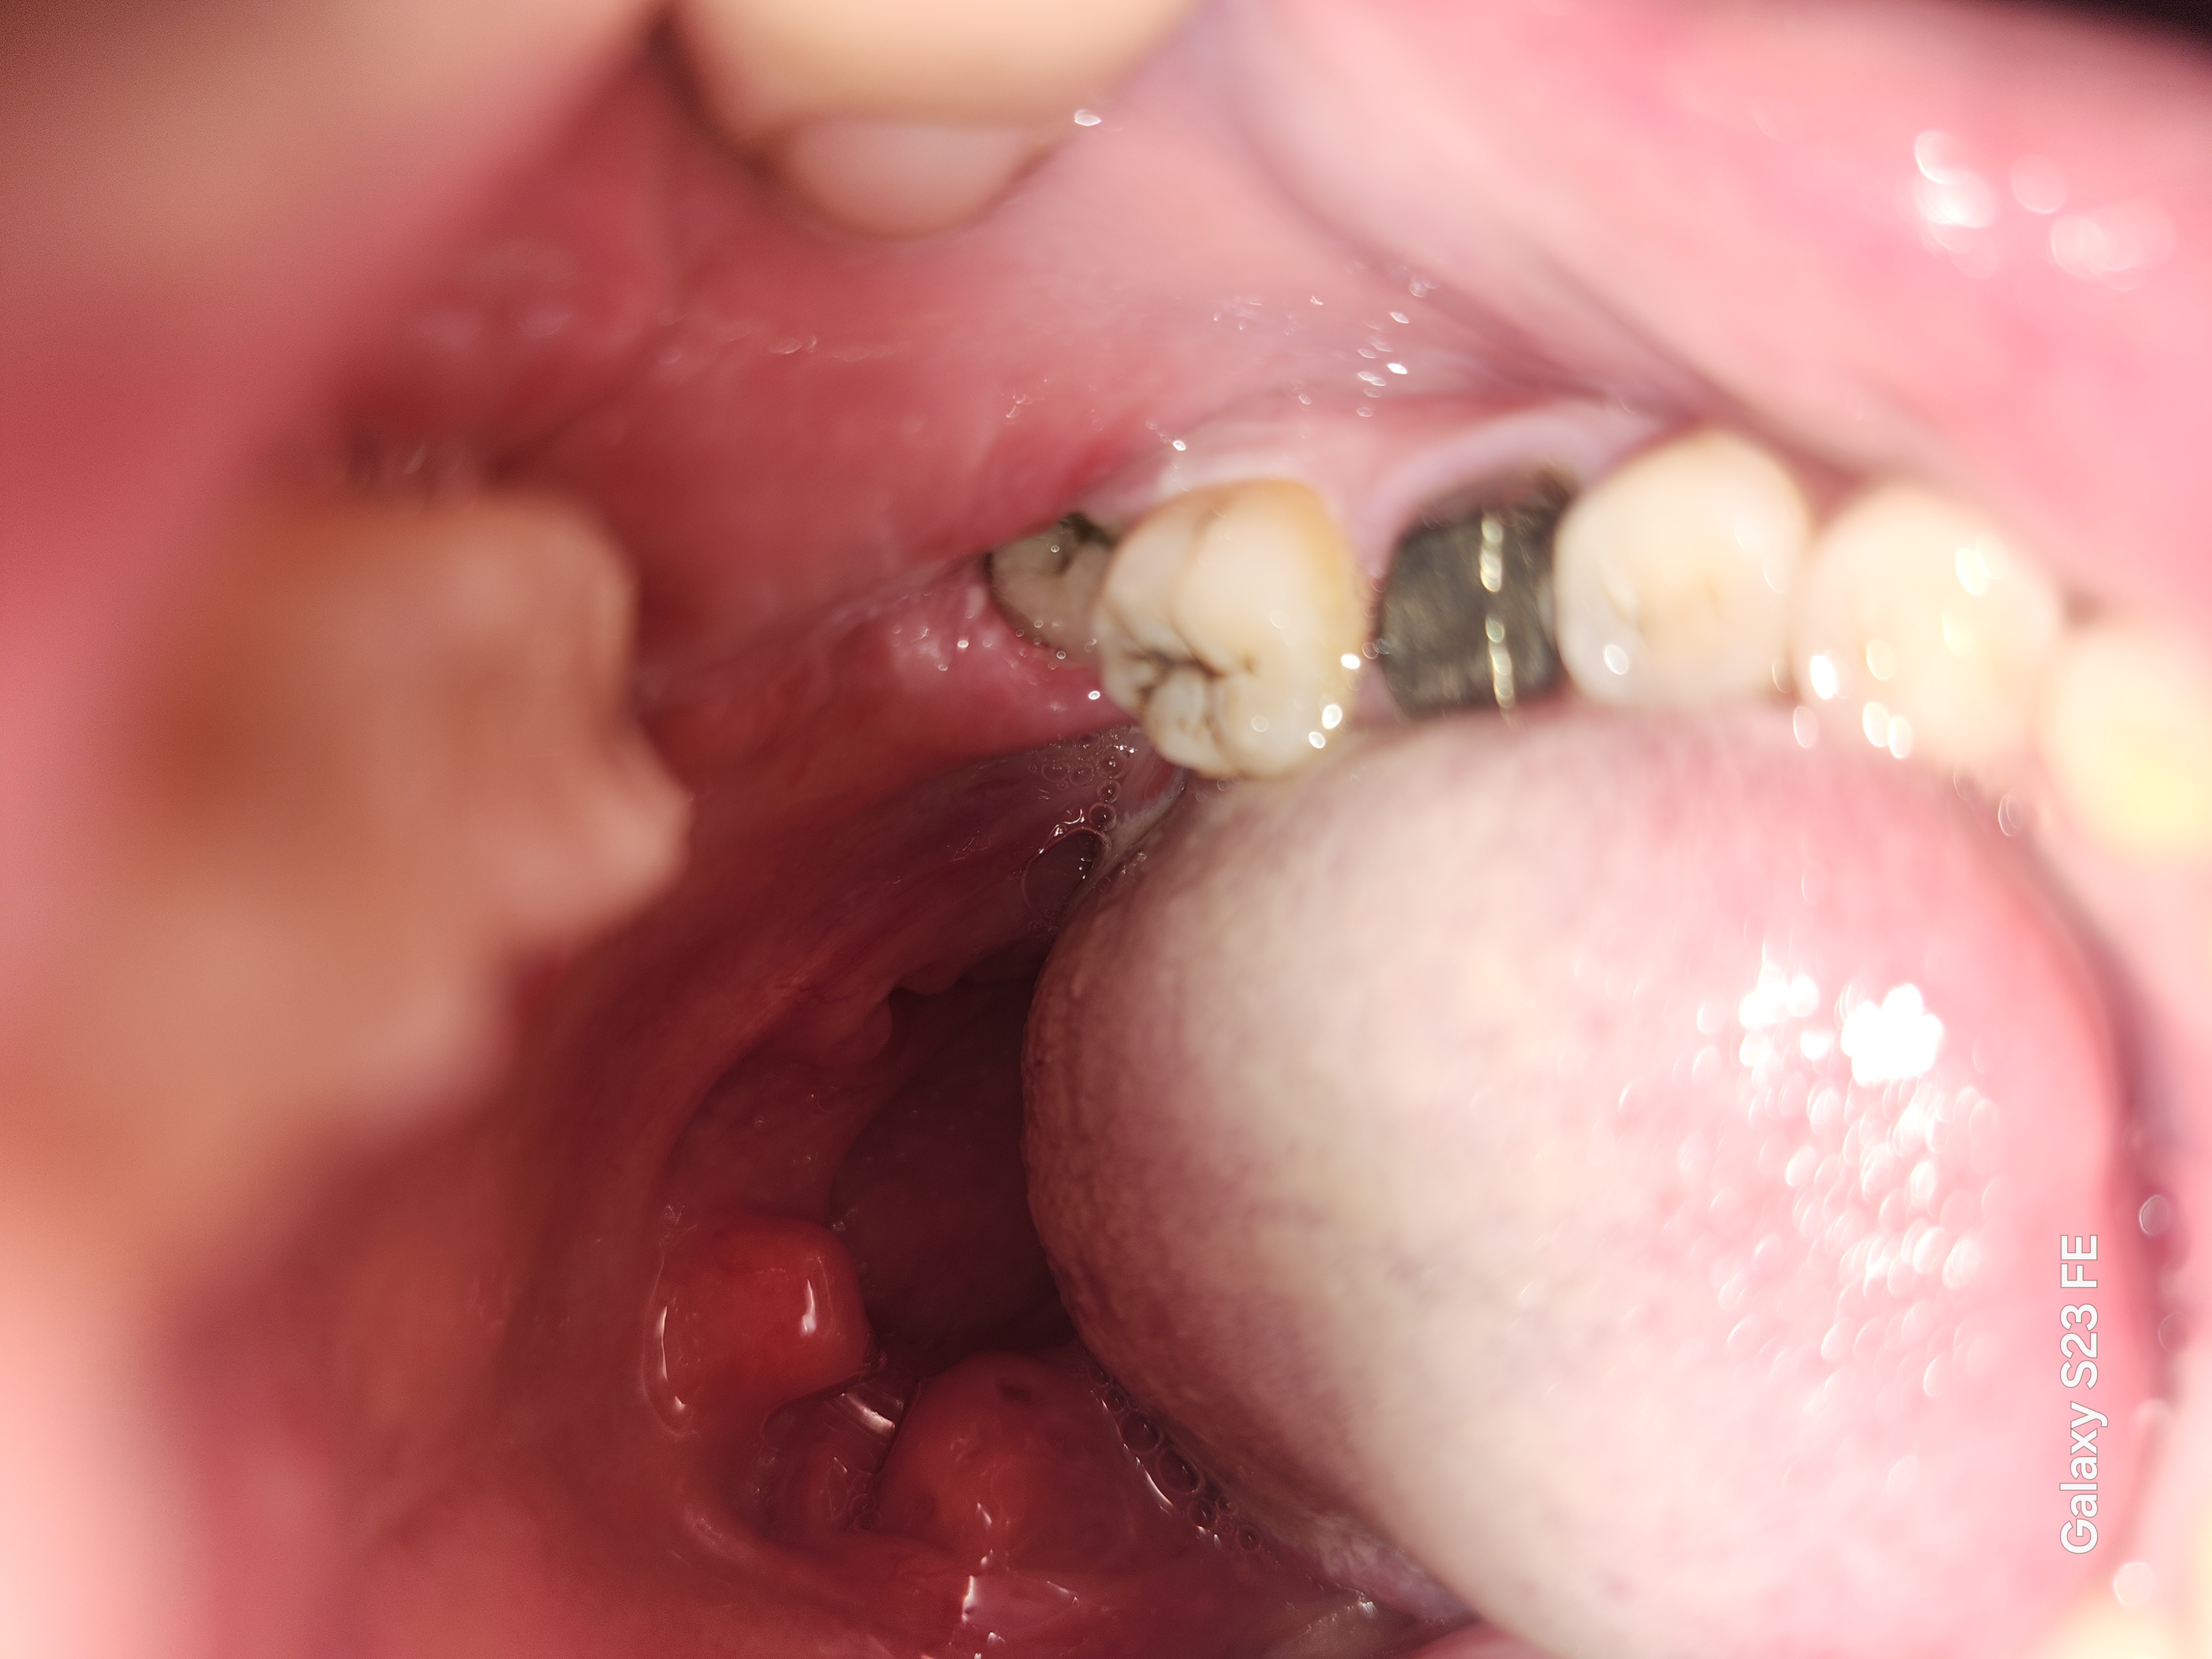

親知らず抜歯後、4日経っても痛みが酷く、ドライソケットではないかと不安です。